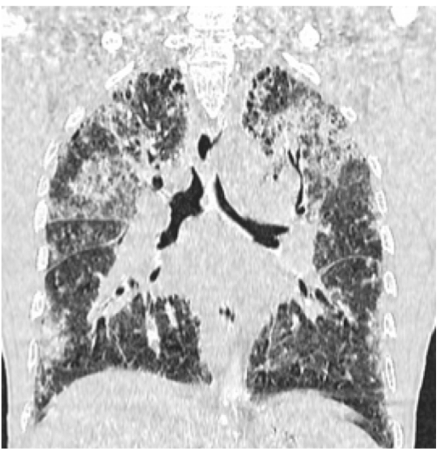

Is this UIP?

No, this is not UIP because this is upper-lobe predominant fibrosis